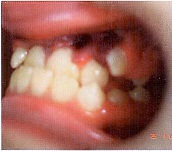

St. localis: гематома слизистой верхней губы, отек и гиперемия слизистой в области верхних резцов, гематома в области зубов 2.2, 2.3, обратное резцовое перекрытие в области 1.1, 2.1, 2.2. Экструзия зубов 1.1, 2.1 и 2.2, подвижность зубов 1.1, 2.1 и 2.2 II степени (Рис. 3).

Рис. 3

Окклюзия: смыкание в области первых моляров и клыков по III классу. Сужение и укорочение верхнего зубного ряда, по трансверзали бугровые контакты. Обратное

резцовое перекрытие около 3 мм. Вестибулярное положение зуба 2.3.